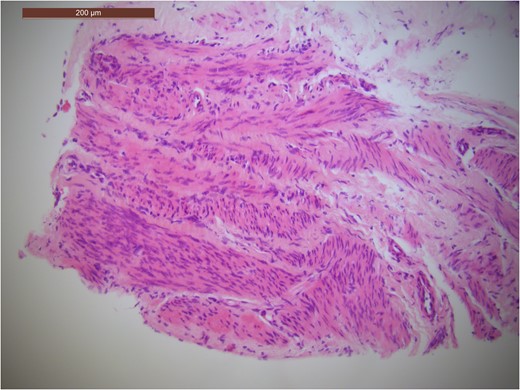

A CT guided fine needle aspirate (FNA) was carried out ~1 month after her initial surgery. Histopathology showed abnormal smooth muscle proliferation within lung parenchyma (Fig. 3). The smooth muscle cells were positive for smooth muscle Actin, Vimentin and Desmin protein (Fig. 4). This is suggestive of a smooth muscle tumour (which in the lung is most likely to be metastatic) or lymphangioleiomyomatosis. The immunohistochemistry favoured the diagnosis of a smooth muscle tumour.